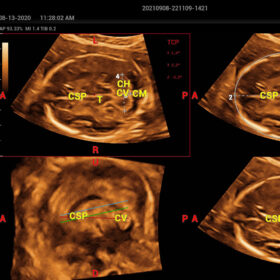

- Smart Scene 3D – Full Stack smartness obstetric solution empowered by ZST+. Comprehensive 3D/4D OB imaging solution with comprehensive fetal parts coverage.

One Key for favorite fetal part imaging, reducing manual adjustment - Smart Face – Automatic removal of occlussions over fetal face with one click